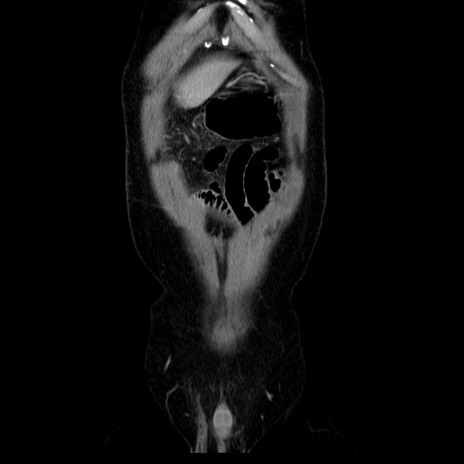

横断像

【症例】40歳代男性

【現病歴】2日前から胃痛あり。徐々に周期的な激痛に変化した。本日になっても激痛があるため受診。

【身体所見】意識清明、BT 38-39℃台あり、腹部:膨満、やや硬、右下腹部に圧痛あり。

【データ】WBC 8500、CRP 23.26